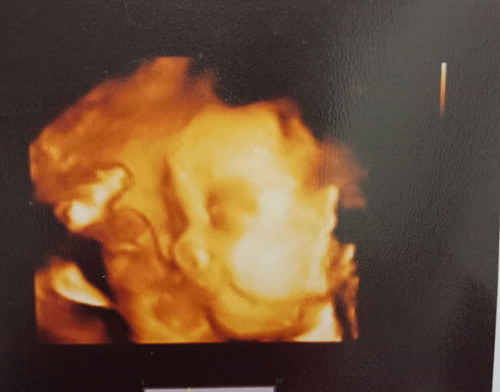

แม่ๆคะช่วง31Weekน้ำหนักลูกได้เท่าไหร่คะนี้ พึ่งได้1200เองคะ กังวลกลัวลูกตัวเล็ก

น้อยไปค่ะแม่ ตอนท้อง29w นน.ลูก1,236ค่ะ นน.น้องตกเกรณฑ์แล้วค่ะแม่ แม่รีบบำรุงเลยนะก่อนนน.จะนน.คงที่ อัดไข่ เนื้อ หมู นม นมพวกนมสัตว์ช่วยได้เยอะค่ะ เช่น นมวัว นมแพะ

นี่จ้า